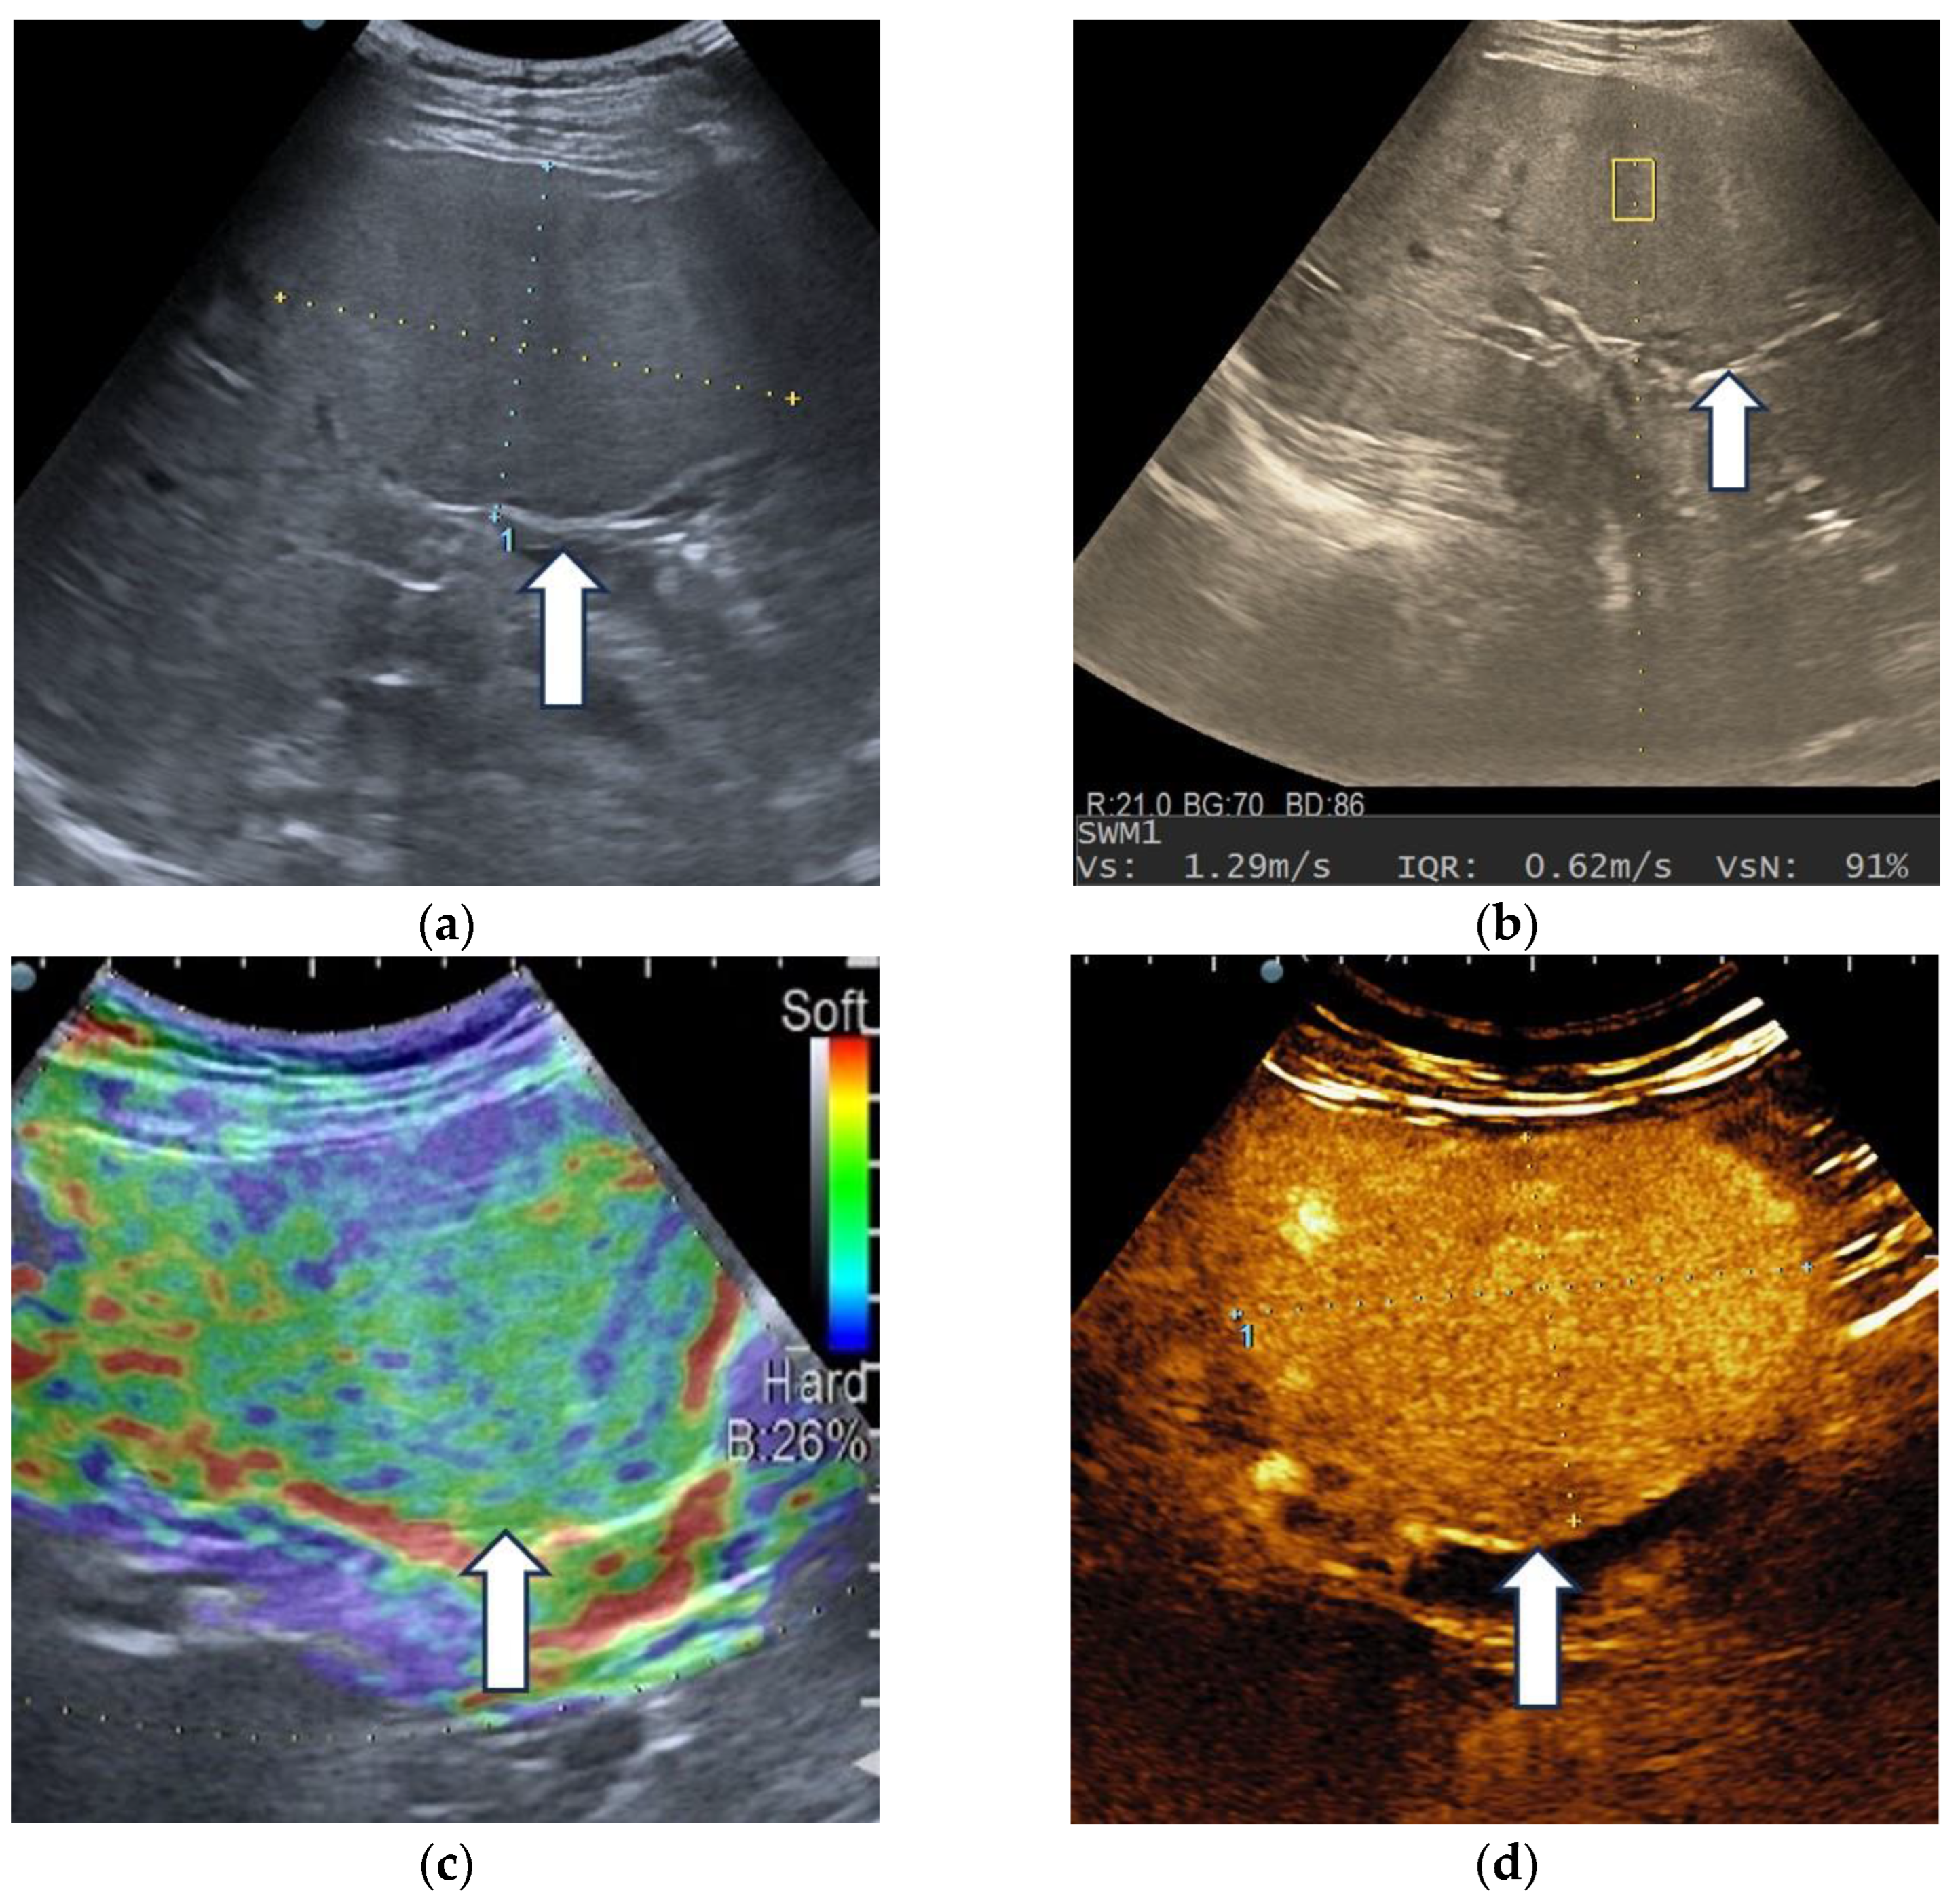

3.3. Shear Wave Measurements in Liver Tumors

3.4. Real-Time Tissue Elastography

| Tumor Type | Mean Vs (m/s) | Range |

|---|---|---|

| HCCs | 1.59 ± 0.29 | 1.07–2.31 m/s |

| Non-HCC malignancies | 1.9 ± 0.42 | 1.34–3 m/s |

| Benign tumors | 1.75 ± 0.4 | 1.36–2.51 m/s |

| Sensitivity (95% CI) | Specificity (95% CI) | PPV (95% CI) | NPV (95% CI) | Accuracy (95% CI) |

|---|---|---|---|---|

| 54.76% | 82.35% | 88.46% | 42.42% | 62.71% |

| (38.67–70.15%) | (56.57–96.20%) | (72.59–95.69%) | (33.09–52.34%) | (49.15–74.96%) |